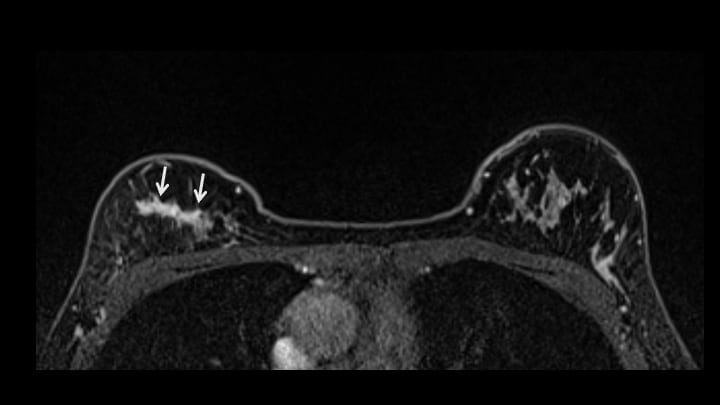

2. T1強調画像(造影前)

左に比較し、右乳腺上部には収縮性の変化(構築の乱れ)が認められる(矢印)。

3. 脂肪抑制T2強調画像(造影前)

T1WIと同様構築の乱れが認められる(矢印)。